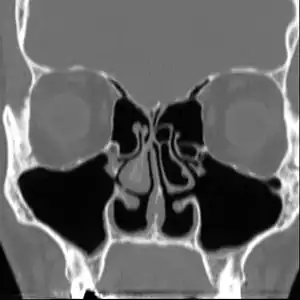

Altered nasal anatomy after bilateral subtotal inferior turbinectomy. | |